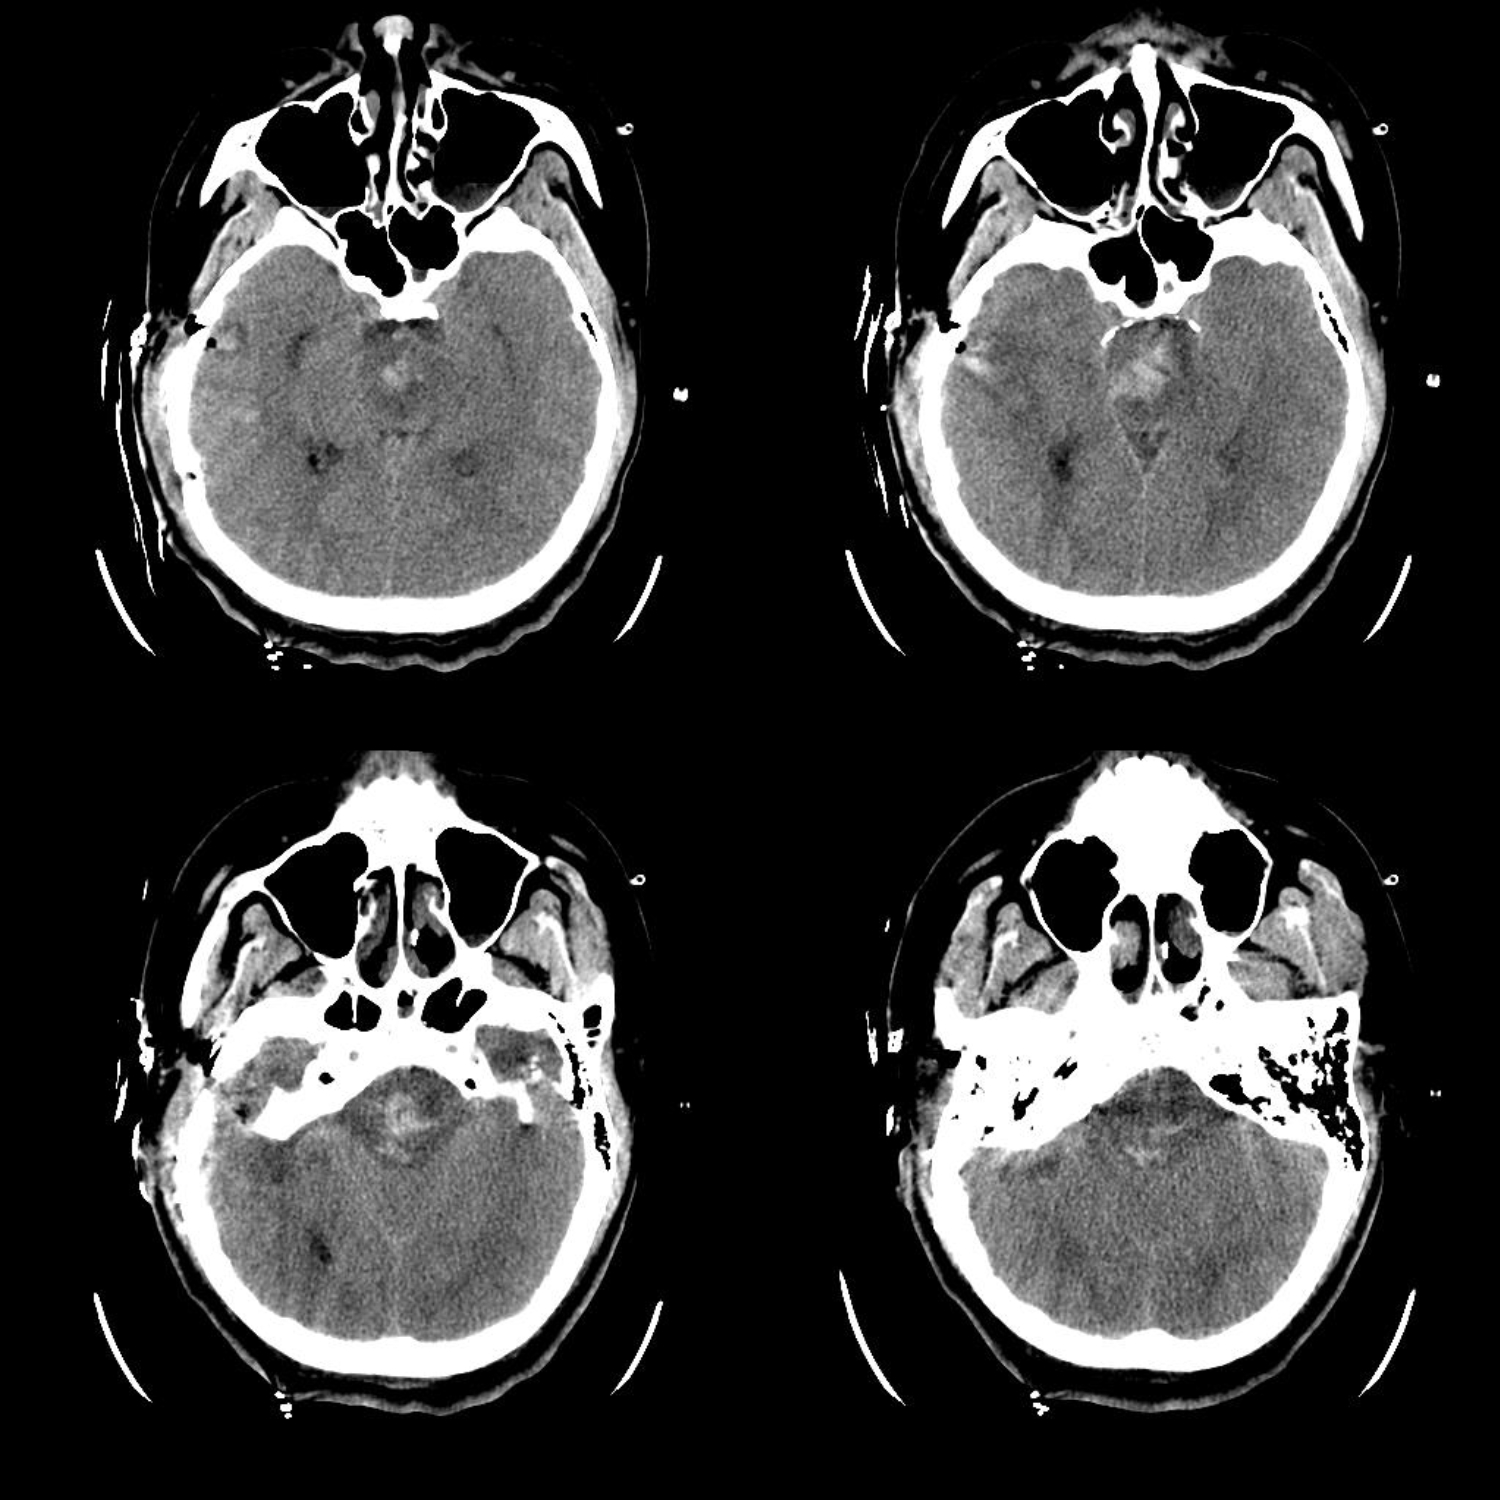

患者25岁男性,主因突发意识不清2.5小时入院,急诊行气管插管呼吸机辅助呼吸。

术前CT提示脑干出血,量约10ml,家属积极要求手术治疗,考虑血肿位置较高,拟行颞下入路,术前先行脑室穿刺释放脑脊液降颅压

术后CT显示脑干血肿大部分清除